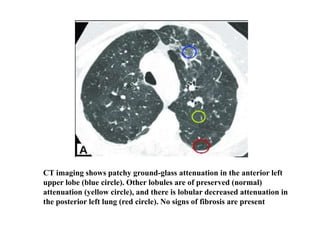

Three-density sign/

CT imaging shows patchy ground-glass attenuation in the anterior left

upper lobe (blue circle). Other lobules are of preserved (normal)

attenuation (yellow circle), and there is lobular decreased attenuation in

the posterior left lung (red circle). No signs of fibrosis are present

Three-density pattern

• Ground glass opacification

• Mosaic attenuation with zonesof diminished

attenuation/hypoperfusion.

• Areas of normal-appearing parenchyma.